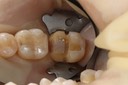

Wayne Chin #30 pre-op

Wayne Chin #30 prep

Wayne Chin #30 finish